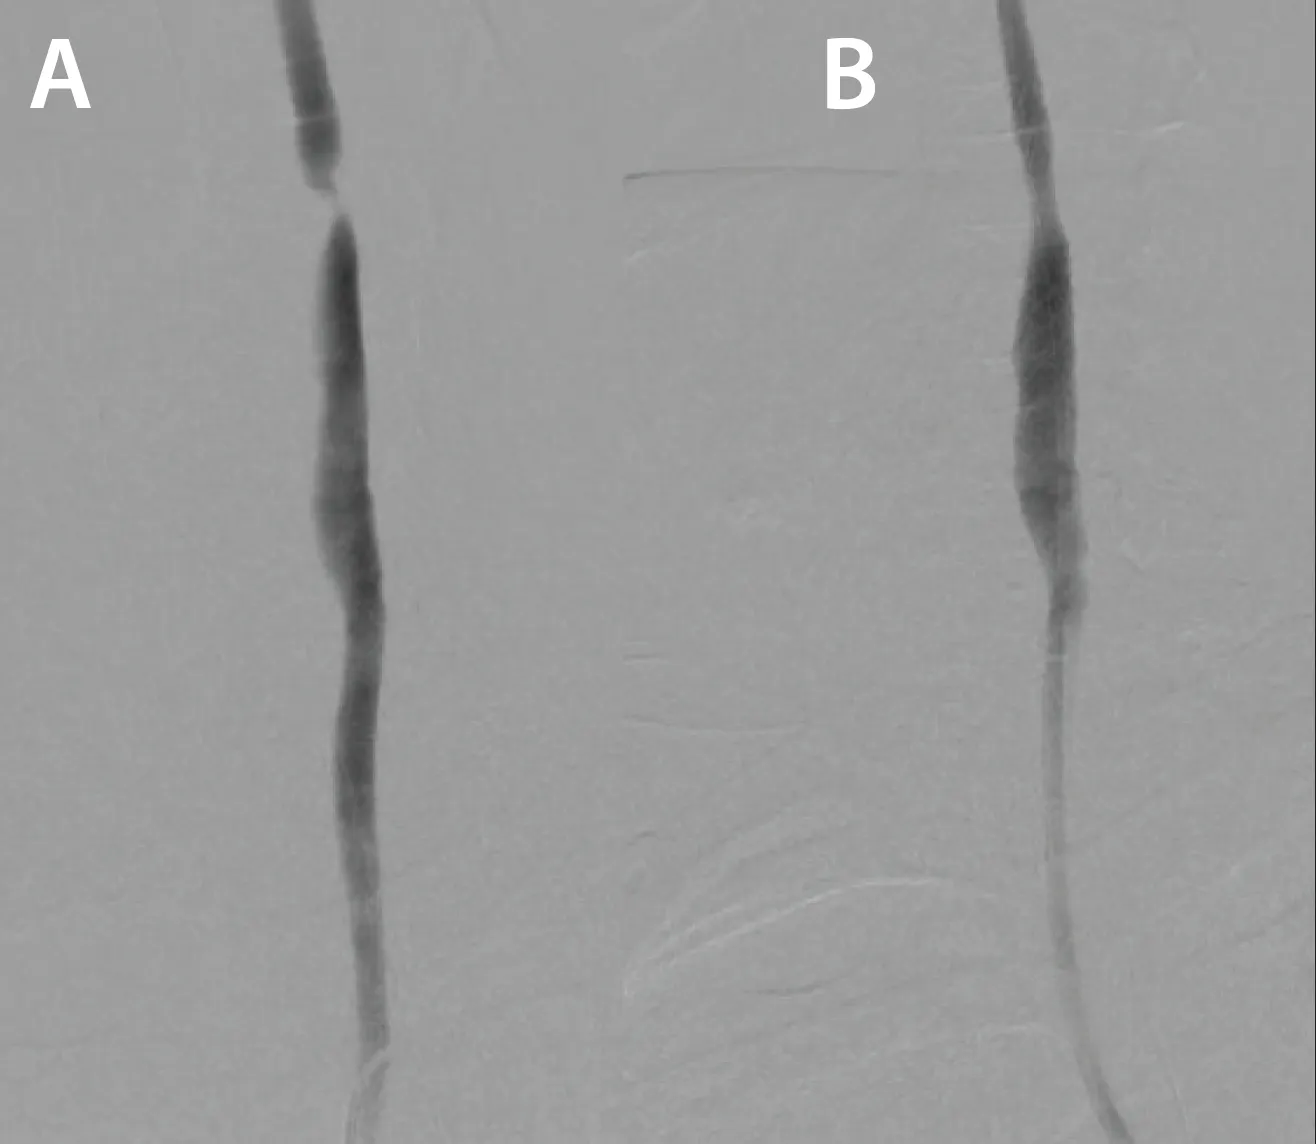

A pigtail catheter was positioned in the aortic arch and an arch aortogram was obtained, confirming the presence of a type I aortic arch without significant calcification. Significant tortuosity was noted in the innominate artery (Figure 2). The catheter was then switched out for a 5-F vertebral shaped catheter that was used to cannulate the left CCA, and carotid and cerebral angiograms were obtained. These showed no significant stenosis of the left carotid system, with cerebral angiograms showing antegrade filling of the left anterior artery and middle cerebral artery (MCA), as well as contralateral filling of the right anterior cerebral artery (ACA) and MCA (Figure 3).

Figure 2. Significant tortuosity noted in the innominate artery.

The vertebral catheter was then used to cannulate the innominate artery and advanced over a 0.038-inch Glidewire to the right CCA. Subsequent carotid and cerebral angiography showed no significant stenosis of the CCA and a widely patent external carotid artery (ECA). A critical subtotal occlusion of the proximal ICA (Figure 4) was noted, with sluggish TICI (thrombolysis in cerebral infarction) 1 to 2 flow in the distal ICA into the MCA; the ACA was not filling antegrade (Figure 5).

Figure 4. Critical subtotal occlusion of the proximal ICA.